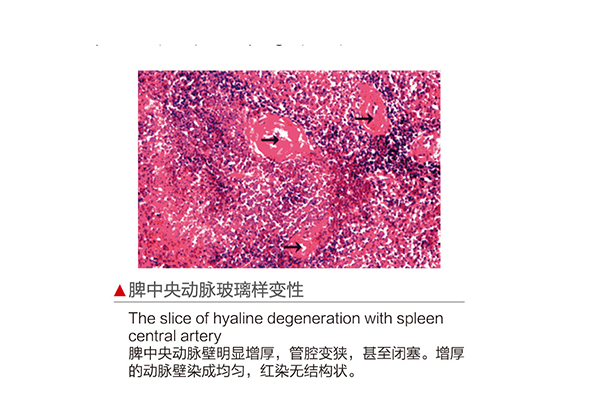

推荐产品

苏模苏医教的产品结构精确细微细致,说明详细,是理想的直观教具。